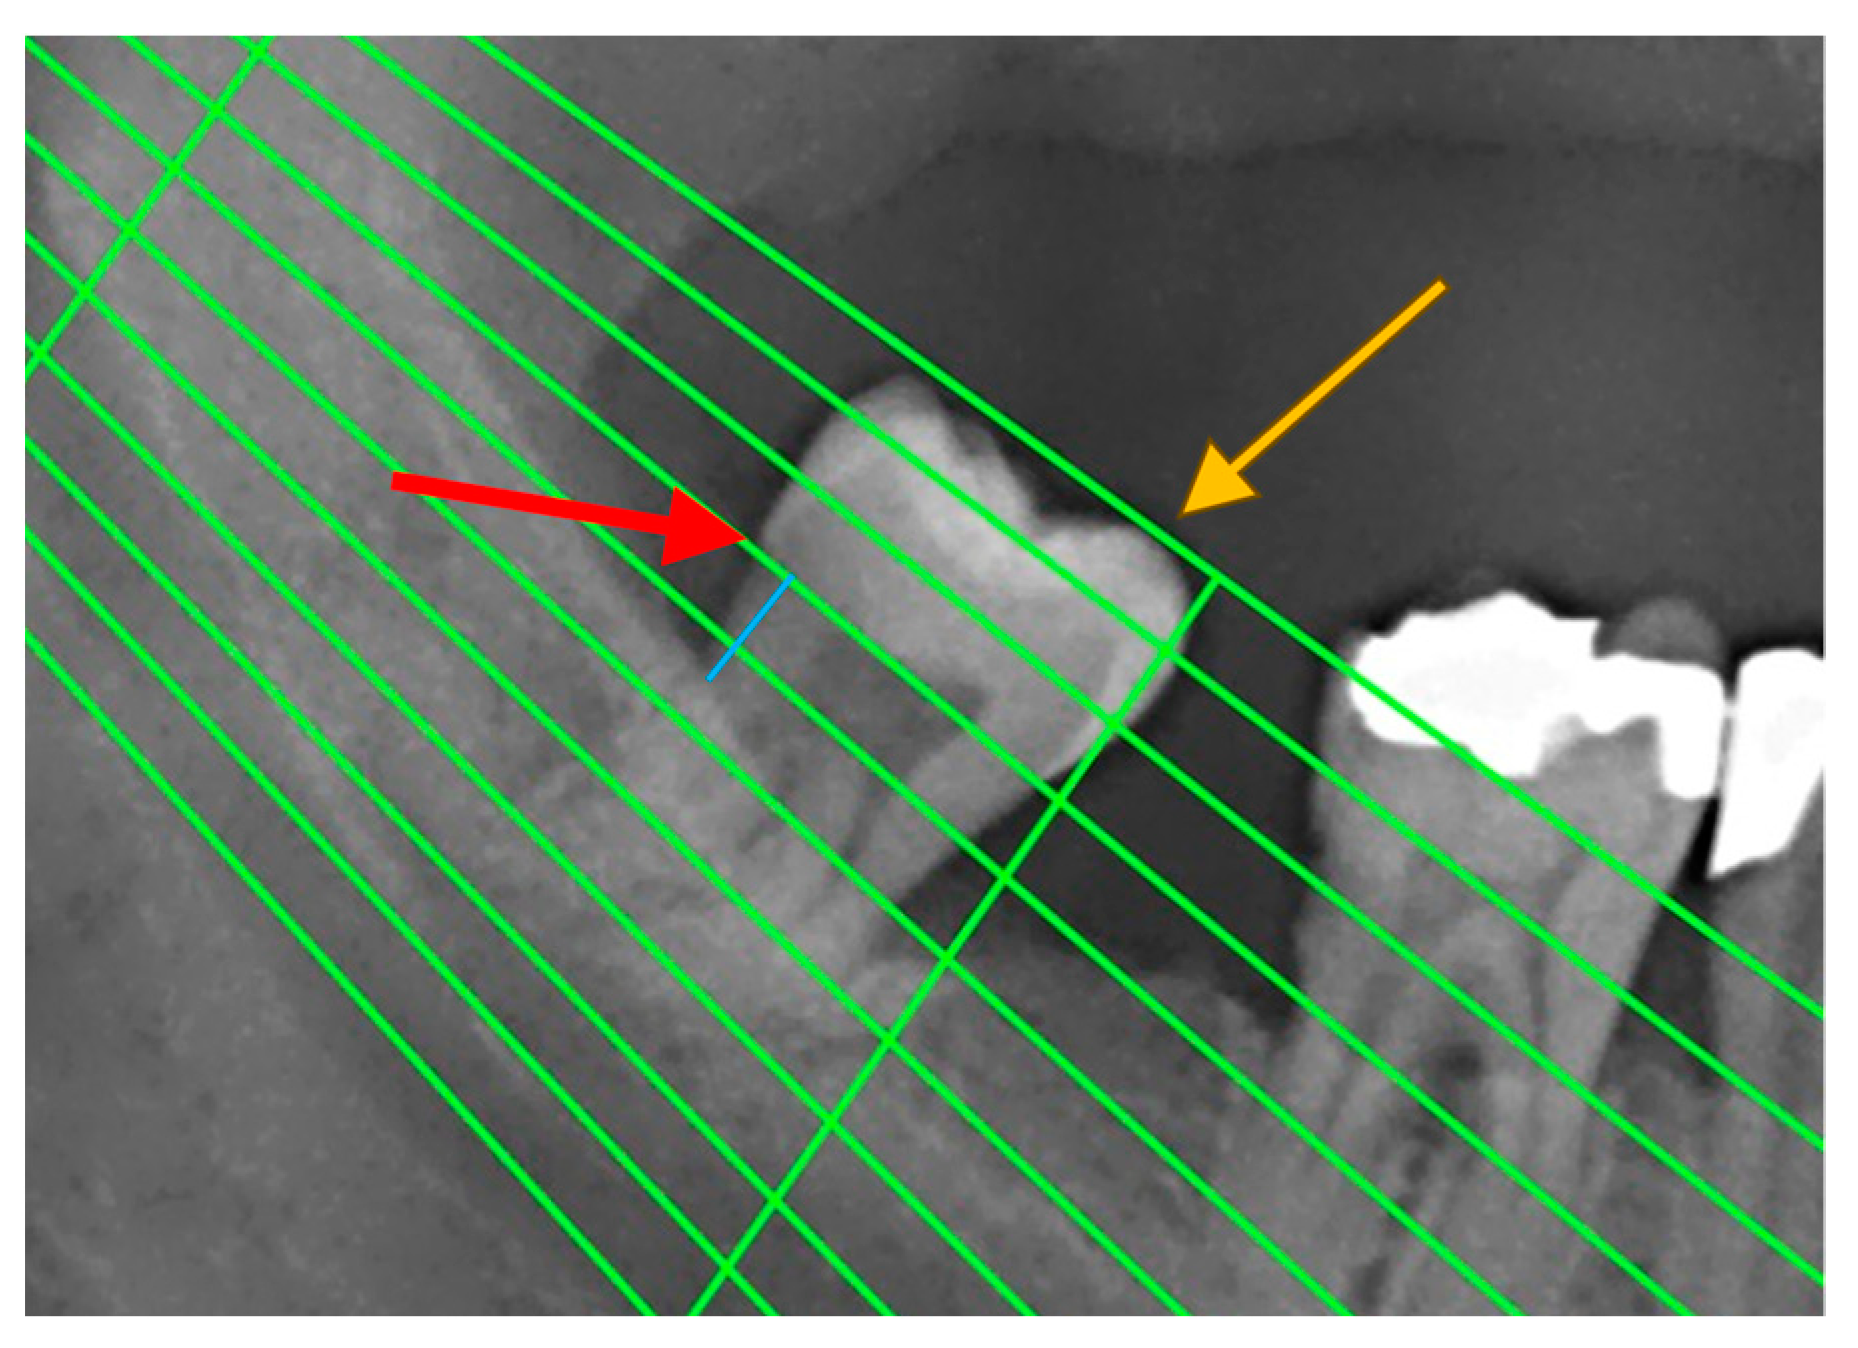

Periodontal disease was also confirmed by measuring radiographic bone loss (RBL) on dental panoramic tomograms (DPTs). All DPTs were taken using an Orthophos XG 3D device (Sirona Dental Systems GmbH, Bensheim, Germany) in the Department of Dentistry at the Faculty of Medical Sciences, University of Kragujevac. To clarify alveolar bone levels and root apices of the entire dentition, all radiographic images were enhanced in the picture editing software GIMP (GNU Image Manipulation Program, Software version 2.10) and were subsequently printed and used for measuring the distance [22] (Figure 1). Periodontal disease staging was assessed from the classification of 2018 [19,23] with extracted referent values by stages (Table 1).

Figure 1.

An example of measuring radiographic bone loss using a Schei ruler, where the red arrow indicates the line tangent to the cementoenamel junction, the yellow arrow indicates the line tangent to the highest point of the crown, and the blue line represents approximately 1.5 fields between the cementoenamel junction and the alveolar bone level.